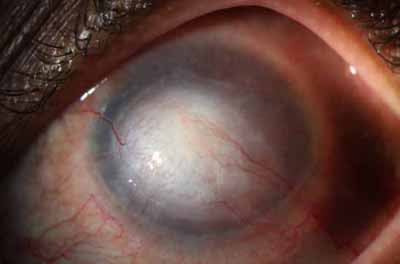

Evolución clínica

Cuando el diagnóstico es temprano y la infección por Acanthamoeba es superficial(intraepitelial), su resolución con el tratamiento será más rápido, minimizando las secuelas respecto a lo que ocurre después de ese tiempo, cuando el organismo ya esta infiltrando y comprometiendo el estroma corneal.

El cuadro clínico inicial progresa, aparecen infiltrados estromales anteriores focales o difusos, edema circunscrito y a veces perineuritis

En su evolución se observará aumento del edema, aparición de un anillo inmunológico (Wessely), agrandamiento y coalescencia de los infiltrados que progresan hacia la formación de un absceso, queratolisis superficial, adelgazamiento y perforación corneal.

La vascularización y el hipopion son poco frecuentes en los estadios tempranos de la queratitis. Con el tiempo, en los estados avanzados de invasión estromal, aparecen vasos estromales